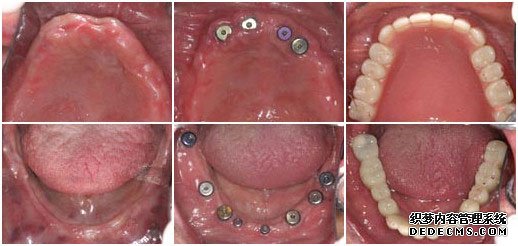

种植牙前                             植入种植体后                   套上烤瓷牙冠完成手术

牙症:全口牙缺失

检查:全口牙齿缺失,无能明显依托的牙根,X片显示根尖无异常

美牙方案:通过口腔数码内窥镜、口腔全景机及微创无痛设备,精密观测口腔内的状况,运用先进的瑞士ITI种植牙技术进行种植。

美牙后:全口牙修复成功,恢复了咀嚼功能,饮食和说话都能自如。

美牙技术:韩国登腾Dentium

美牙时间:6个月

王老伯来武汉爱齿尔口腔就诊的时候,情况非常糟糕,在医生的检查下,发现他口腔内的牙齿全部缺失,并没有可持久依托的牙根,面对这一情况,医生只有建议王老伯做种植牙。虽说种植牙的治疗时间较长,但是对于王老伯这样的牙齿状况,种植牙是一种十分理想的选择。

由于王老伯今年已经61岁,所以在植入种植体后的恢复时间比一般人要常一些,花了将近5个月的时间才长好,但这并不影响种植牙的效果。最后在套烤瓷牙冠的时候,王老伯的家人也感到十分惊异,因为种出来的牙齿不但美观漂亮,甚至比王老伯之前的真牙还要逼真,一下子王老伯的牙齿看起来仿佛只有20多岁。而最最高兴的还是王老伯,他说:“我以前戴的全口活动假牙,吃东西不方便,连老伴弄的饭菜也都不想吃,可这次种牙太成功了,真是那句老话:‘牙好,胃口就好啊!’,太感谢你们了”